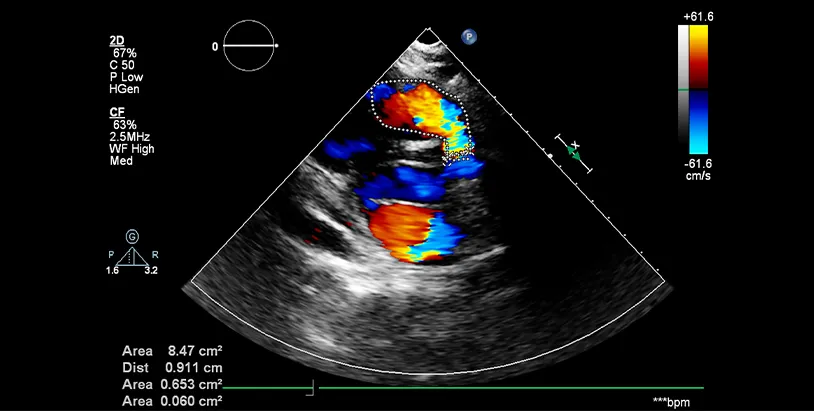

Colour Doppler Imaging equipment at Sun Imaging & Diagnostics